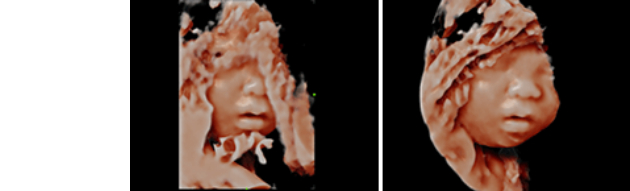

Smart Face provides a fast and intelligent optimization for fetal face with simply one-touch operation. It immediately removes occlusions, such ascord, placenta, uterus and extremities, in the volume data and eliminates unwanted noise information, so finally generates an optimal view of the fetal face with more simplicity.